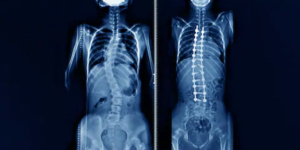

La escoliosis es una curvatura anormal de la columna vertebral. El Dr. Valle Folgueral diagnostica y corrige estos casos para mejorar postura y función.